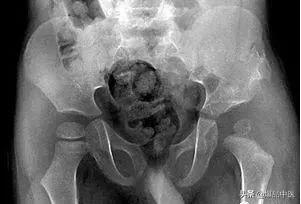

骨盆骨折

1、股骨颈或股骨粗隆间骨折:多见于老年人;患肢常有短缩外旋畸形,大粗隆上移;X线片可鉴别。

叩击试验阳性。合并病理性脱位者大转子升高,患肢短缩,且呈屈曲、内收位。X线检查对本病的早期诊断很重要,应拍骨盆正位片,仔细对比两侧髖关节。单纯滑膜结核的变化有:①患侧髋臼与股骨头骨质疏松,骨小梁变细,骨皮质变薄。②由于骨盆前倾,患側闭孔变小。③患侧的滑膜与关节囊肿胀。④患侧髋关节间隙稍宽或稍窄,晚期全关节结核关节软骨面破坏,软骨下骨板完全模糊。结核菌素试验适用于4岁以下的儿童,髋关节穿刺液做涂片检查和化脓菌及结核菌素培养,对本病诊断有一定价值,但髋关节位置深在,有时穿刺不一定成功,手术探查取组织活检,是最准确的诊治方法。